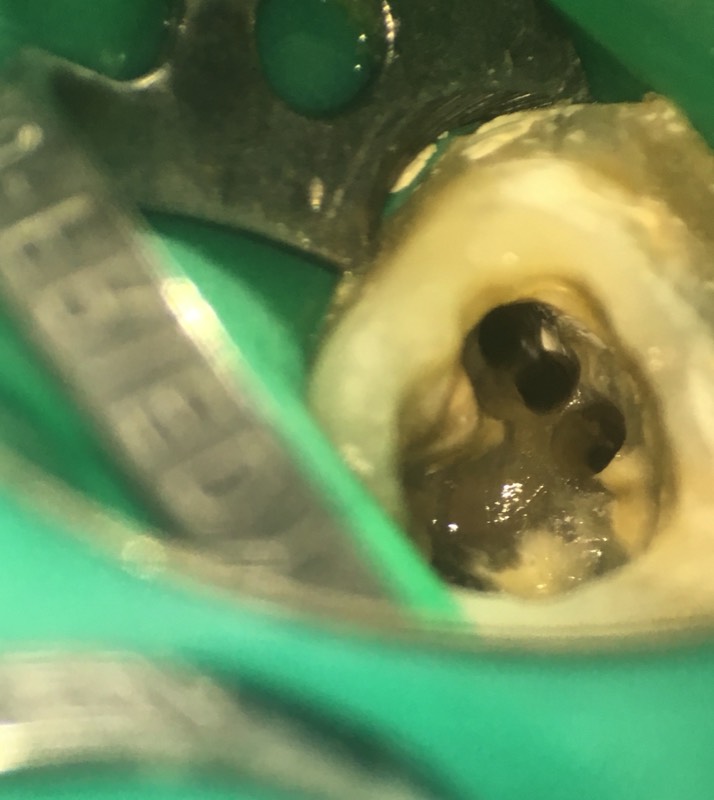

Endodontie

Die Wurzelkanalbehandlung (Endodontologie) ist bei Entzündungen des Zahnmarks oder des Knochens an der Wurzelspitze die einzige Möglichkeit, einen Zahn dauerhaft zu erhalten. Es handelt sich hierbei um eine der schwersten und kompliziertesten Behandlungen, die an einem Zahn durchgeführt werden können. Wir nutzen daher in der Regel ein OP Mikroskops und ganz spezielle Techniken und Instrumente.